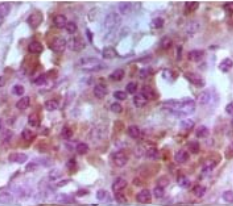

Foxp3 Mouse Monoclonal antibody[2A11G]

The transcription factor Foxp family includes Foxp1, Foxp2, and Foxp3. The Foxp3 (50KDa)plays a key role in CD4(+) CD25(+) regulatory T cell function and represents a specific marker for these cells. Despite its strong association with regulatory T cell function, in humans little is known about the frequency of CD4(+) CD25(+) cells that express FOXP3 protein nor the distribution of these cells in vivo. FOXP3 may be a master regulatory gene and a more specific marker of regulatory T cells than other T cells.

IHC    1/200 - 1/1000